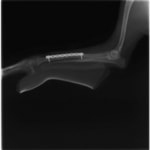

症例:交通事故による椎体脱臼

柴犬:9歳、避妊雌

交通事故直後、胸腰部に激しい疼痛、両後肢に完全麻痺を認め、シェフシェリントン徴候を呈していました。レントゲン検査において、第11-12胸椎間の脱臼が認められました。

脊髄の減圧、脊柱管の再構築・安定化を目的に、片側椎弓切除術およびMatrixMANDIBLE Plateによる椎体固定を実施しました。

隣接椎体を架橋するようにプレートを設置しました。

術後レントゲン写真